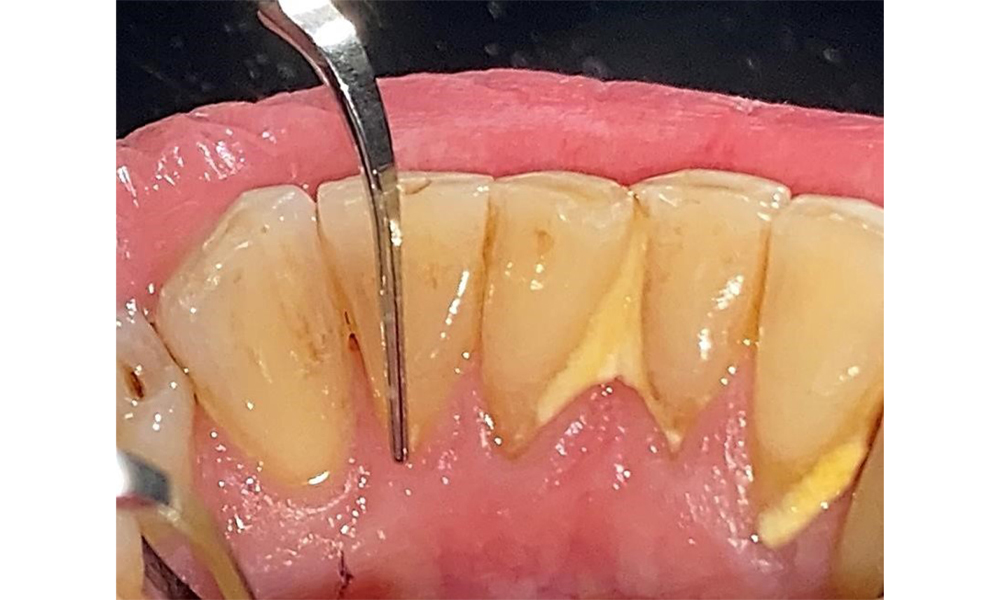

Pacientul prezintă boală parodontală în stadiul II, gradul B (5). Profunzimile clinice de sondare observate, între 1 și 3 mm, se încadrează în limitele fiziologice. Localizat, s-au observat profunzimi de 5 mm, la nivel meziopalatin, atât pe 17, cât și pe 27. Se constată recesiuni generalizate de 1-3 mm, cu pierderi parțiale ale papilelor interdentare (Fig. 2, Fig. 3, Fig. 4)

Examinarea parodontală, incluzând măsurarea adâncimii pungilor parodontale și nivelul de sângerare, este o etapă obligatorie în cadrul fiecărei consultații stomatologice, datorită prezenței parodontozei (fig. 8). Acest lucru va evidenția cerințele terapeutice individuale și va facilita un răspuns rapid la o eventuală evoluție a parodontozei preexistente.

Evaluarea parodontală detaliată, inclusiv consemnarea adâncimii pungilor parodontale, sângerarea la examinarea cu sonda, recesiunile, gradul de afectare a furcației și gradul de slăbire, trebuie efectuată anual.

Nu există limitări în ceea ce privește alegerea metodelor de instrumentare. Sunt esențiale intervențiile subgingivale și supragingivale regulate, pentru prevenirea progresiei bolii - datorită parodontozei preexistente și a riscului ridicat de recidivă. Nu există limitări privind alegerea instrumentelor pentru îndepărtarea mecanică a biofilmului dintr-o perspectivă medicală generală, iar îndepărtarea trebuie efectuată în funcție de necesități. Placa dură și mineralizată, cum ar fi tartrul și concrețiunile, trebuie îndepărtate cu ajutorul pieselor de detartraj manuale sau al scalerului sonic/ultrasonic (Fig. 9) (8, 9).